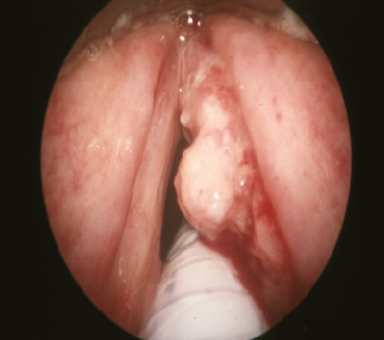

일반적인 인후 검사에서는 후두(혀 뒤쪽 아래쪽에 위치)를 잘 볼 수 없기 때문에 후두암을 조기에 진단하는 유일한 방법은 혀 뒤쪽에 작은 거울을 대거나 후두경(목 뒤쪽으로 내려가는 가늘고 유연한 내시경)을 사용하는 것이라고 합니다. 인후과 전문의가 후두에서 의심스러운 부위를 발견하면 검사를 위해 조직 샘플을 채취하며, 국소 마취 또는 전신 마취를 할 수 있습니다.